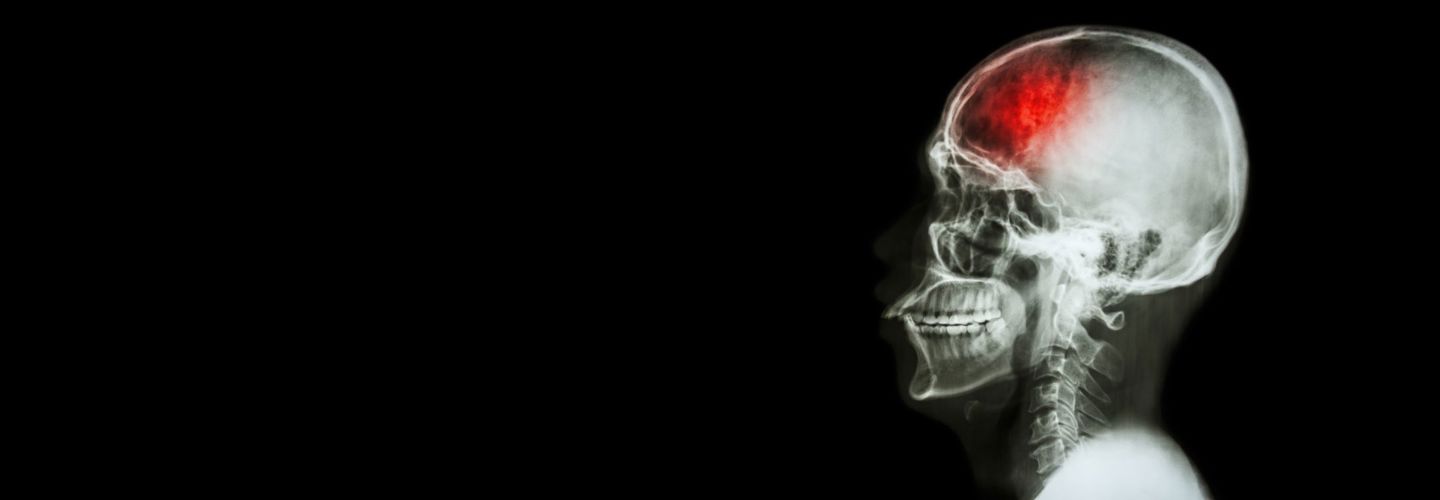

Recognising Stroke Symptoms: Why Every Second Counts

A stroke can affect anyone, regardless of age or health status. For those receiving stroke homecare or living independently, knowing the warning signs is crucial. Quick action can prevent long-term damage and improve recovery outcomes.

Why Acting FAST Matters in Stroke Homecare

Early recognition and response can significantly impact stroke recovery. As providers of comprehensive stroke homecare services, we understand that:

- Quick medical intervention saves brain tissue

- Early treatment improves recovery outcomes

- Faster response means better rehabilitation potential

- Immediate action reduces long-term care needs